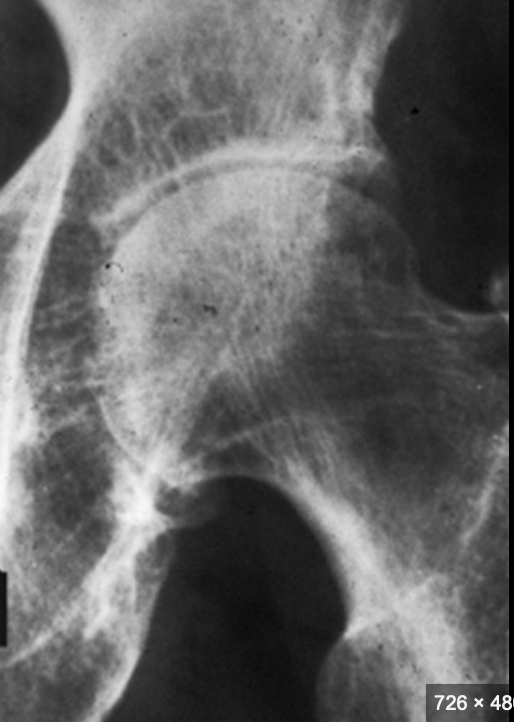

Datos de coxartrosis Rx

A

Disminución del espacio articular

Osteofitos

Esclerosis subcondral

Quistes subcontrates (geodas)

Deformidad

Coxartrosis